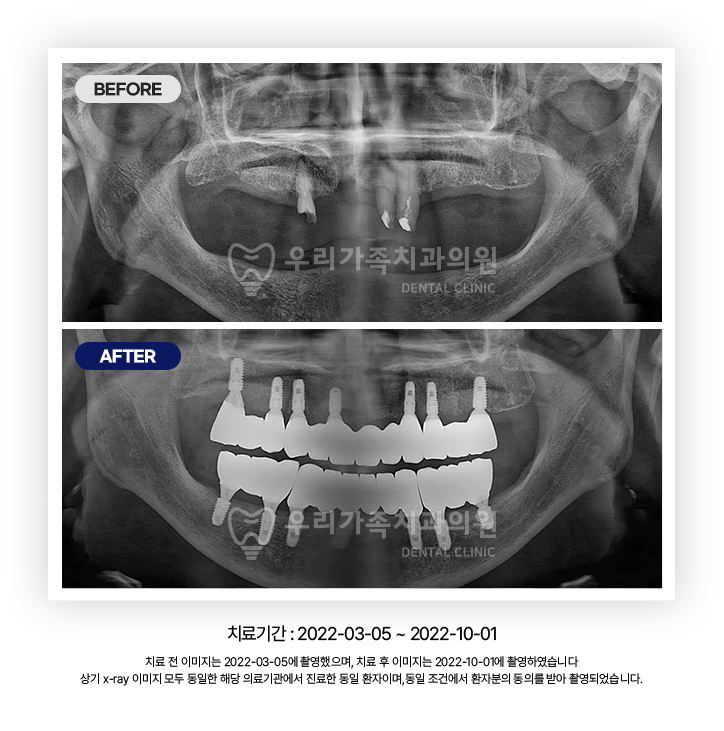

임플란트로 씹는 즐거움을 찾다!